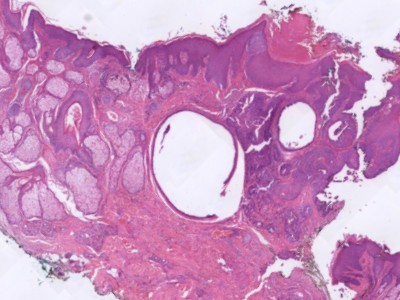

Histologie:Eccriene

hidrocystomen ontstaan door verwijding van de zweetklieren door blokkade van

de afvoergang. Histologisch gaat het om uniloculaire cysten, bekleed met 1

of 2 lagen cuboid epitheel. Ze zitten in de oppervlakkige en mid-dermale

huidlagen. In tegenstelling tot apocriene hidrocystomen worden er geen

apocriene secernerende cellen in het lumen gezien. Eccriene hidrocystomen

kleuren aan met S100 (althans het solitaire type), apocriene niet. De cyste

staat niet in verbinding met de epidermis. De PAS kleuring (periodic

acid-Schiff) is negatief.

Apocriene hidrocystomen zijn uniloculair of

multiloculaire cysten. De cyste wand bestaat uit een enkele of dubbele laag

cuboid-columnair epitheel, omgeven door een myoepitheel laag. De inhoud is

PAS-positief. Zie ook de